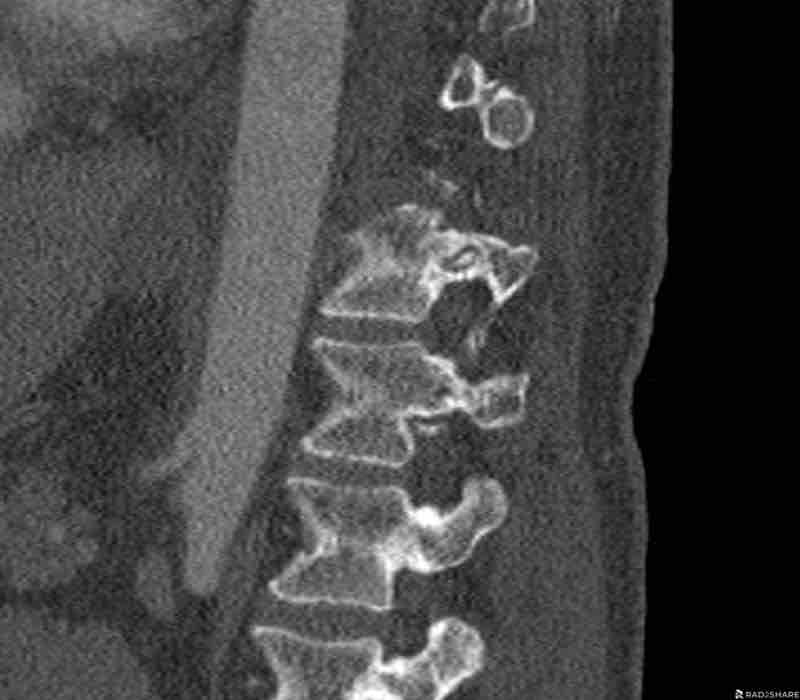

Scroll through the images.

What are the findings?

What is the highest AO-type of injury?

Findings

- Vertical fracture of the posterior border of the vertebral body. It looks a bit odd.

- Again we first have to look for the presence of a type C injury.

- Notice that there is a subtle posterior dislocation of the proximal levels. So this has to be C injury.

Conclusion

Injury type C + A3